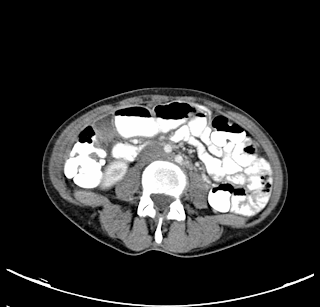

Paciente varón de 55 años que acude a urgencias con dolor en flanco derecho. En la analítica destaca un aumento de la Proteína C reactiva y una marcada leucocitosis. Posteriormente se realiza un TC abdominal:

¿Qué le llama la atención en estas imágenes?

Un aumento de partes blandas paracólico con centro hipodenso.

Neumatosis intestinal. Muy bien, observamos un aumento de partes blandas paracólico derecho con centro hipodenso, hallazgos que son compatibles con un infarto omental, o una apendagitis.

¿Cuál es el tratamiento indicado para dicha patología?

Administración de pauta antiinflamatoria y antibiótica empírica.